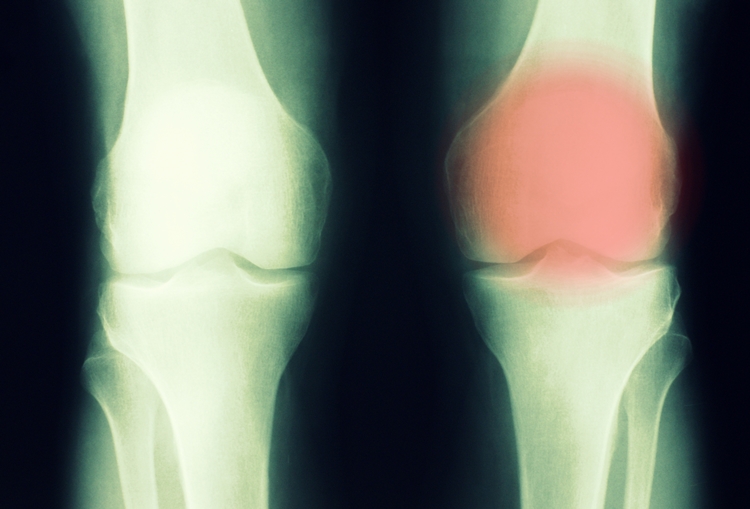

Câncer ósseo é um assunto que merece atenção, uma vez que afeta muitas pessoas ao redor do mundo. Se você ou alguém que você conhece está lidando com essa doença, é importante buscar informações e apoio para enfrentá-la da melhor maneira possível. Os tumores ósseos são considerados uma patologia tecidual grave, que pode ter várias causas e manifestações. Esses tumores podem ser benignos ou malignos, sendo o câncer ósseo uma das formas mais agressivas e preocupantes dessa doença. Uma das principais opções de tratamento para o câncer ósseo é a cirurgia, que pode envolver a remoção de partes do osso afetado ou até mesmo a amputação em casos mais graves. Além disso, a quimioterapia e a radioterapia também podem ser parte do tratamento, dependendo do estágio da doença e das características individuais de cada paciente. É importante ressaltar que o diagnóstico precoce é fundamental para o sucesso do tratamento do câncer ósseo. Portanto, ao perceber sintomas como dor óssea persistente, inchaço, fraqueza ou sensibilidade nos ossos, é essencial buscar atendimento médico para uma avaliação adequada. Embora o câncer ósseo seja uma doença grave, é possível encontrar casos de superação e histórias inspiradoras de pessoas que conseguiram vencer essa doença. O apoio da família, amigos e profissionais de saúde é fundamental nesse processo, proporcionando suporte emocional e informacional ao paciente. Uma alimentação adequada e balanceada, além da prática regular de exercícios físicos, também pode auxiliar na recuperação e no fortalecimento do organismo durante o tratamento do câncer ósseo. Se você está passando por essa situação ou conhece alguém que esteja, saiba que você não está sozinho. Existem diversos grupos de apoio e instituições que oferecem suporte emocional e informações sobre o câncer ósseo. Não hesite em buscar ajuda e compartilhar seus sentimentos e experiências com outras pessoas que possam passar pelo mesmo nesse momento. Em resumo, o câncer ósseo é uma patologia tecidual séria que requer atenção e cuidados específicos. O diagnóstico precoce e o tratamento adequado são fundamentais para assegurar melhores resultados. Nunca deixe de buscar ajuda médica e apoio emocional durante esse processo. Com a assistência adequada, é possível enfrentar o câncer ósseo e encontrar o caminho para a recuperação e a qualidade de vida.

Patologias Teciduais: Tumores Ósseos